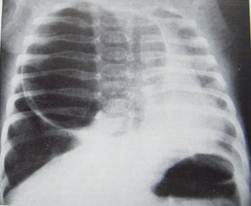

За субкомпенсованої форми клінічні ознаки з'являються у віці 1—3 міс, поступово посилюються розлади дихання, але напади ціанозу короткочасні. Рентгенологічно виявляють збільшення прозорості та слабо виражений легеневий малюнок, поряд з роздутою часткою легені видно тінь колабованої здорової частки, помірне зміщення органів межистіння.